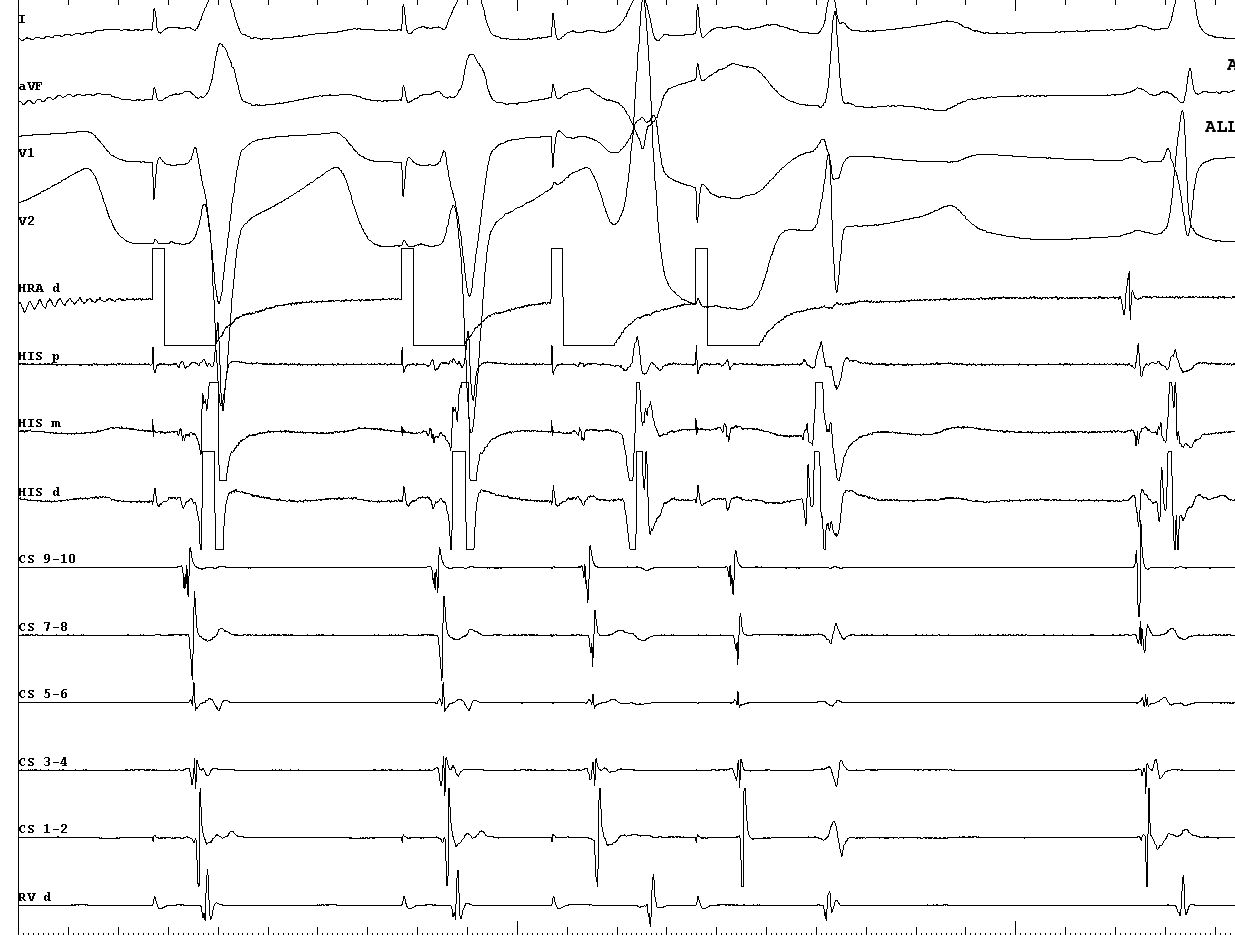

Fasciculoventricular AP

Constant preexcitation

fv_constant_preexcitation.jpg

Constant HV

fv_constant_hv.jpg

Adenosine

fv_adenosine.jpg

Retrograde conduction (22 ms)

fv_retrograde.jpg

Other arrhythmias

fv_other_ap.jpg